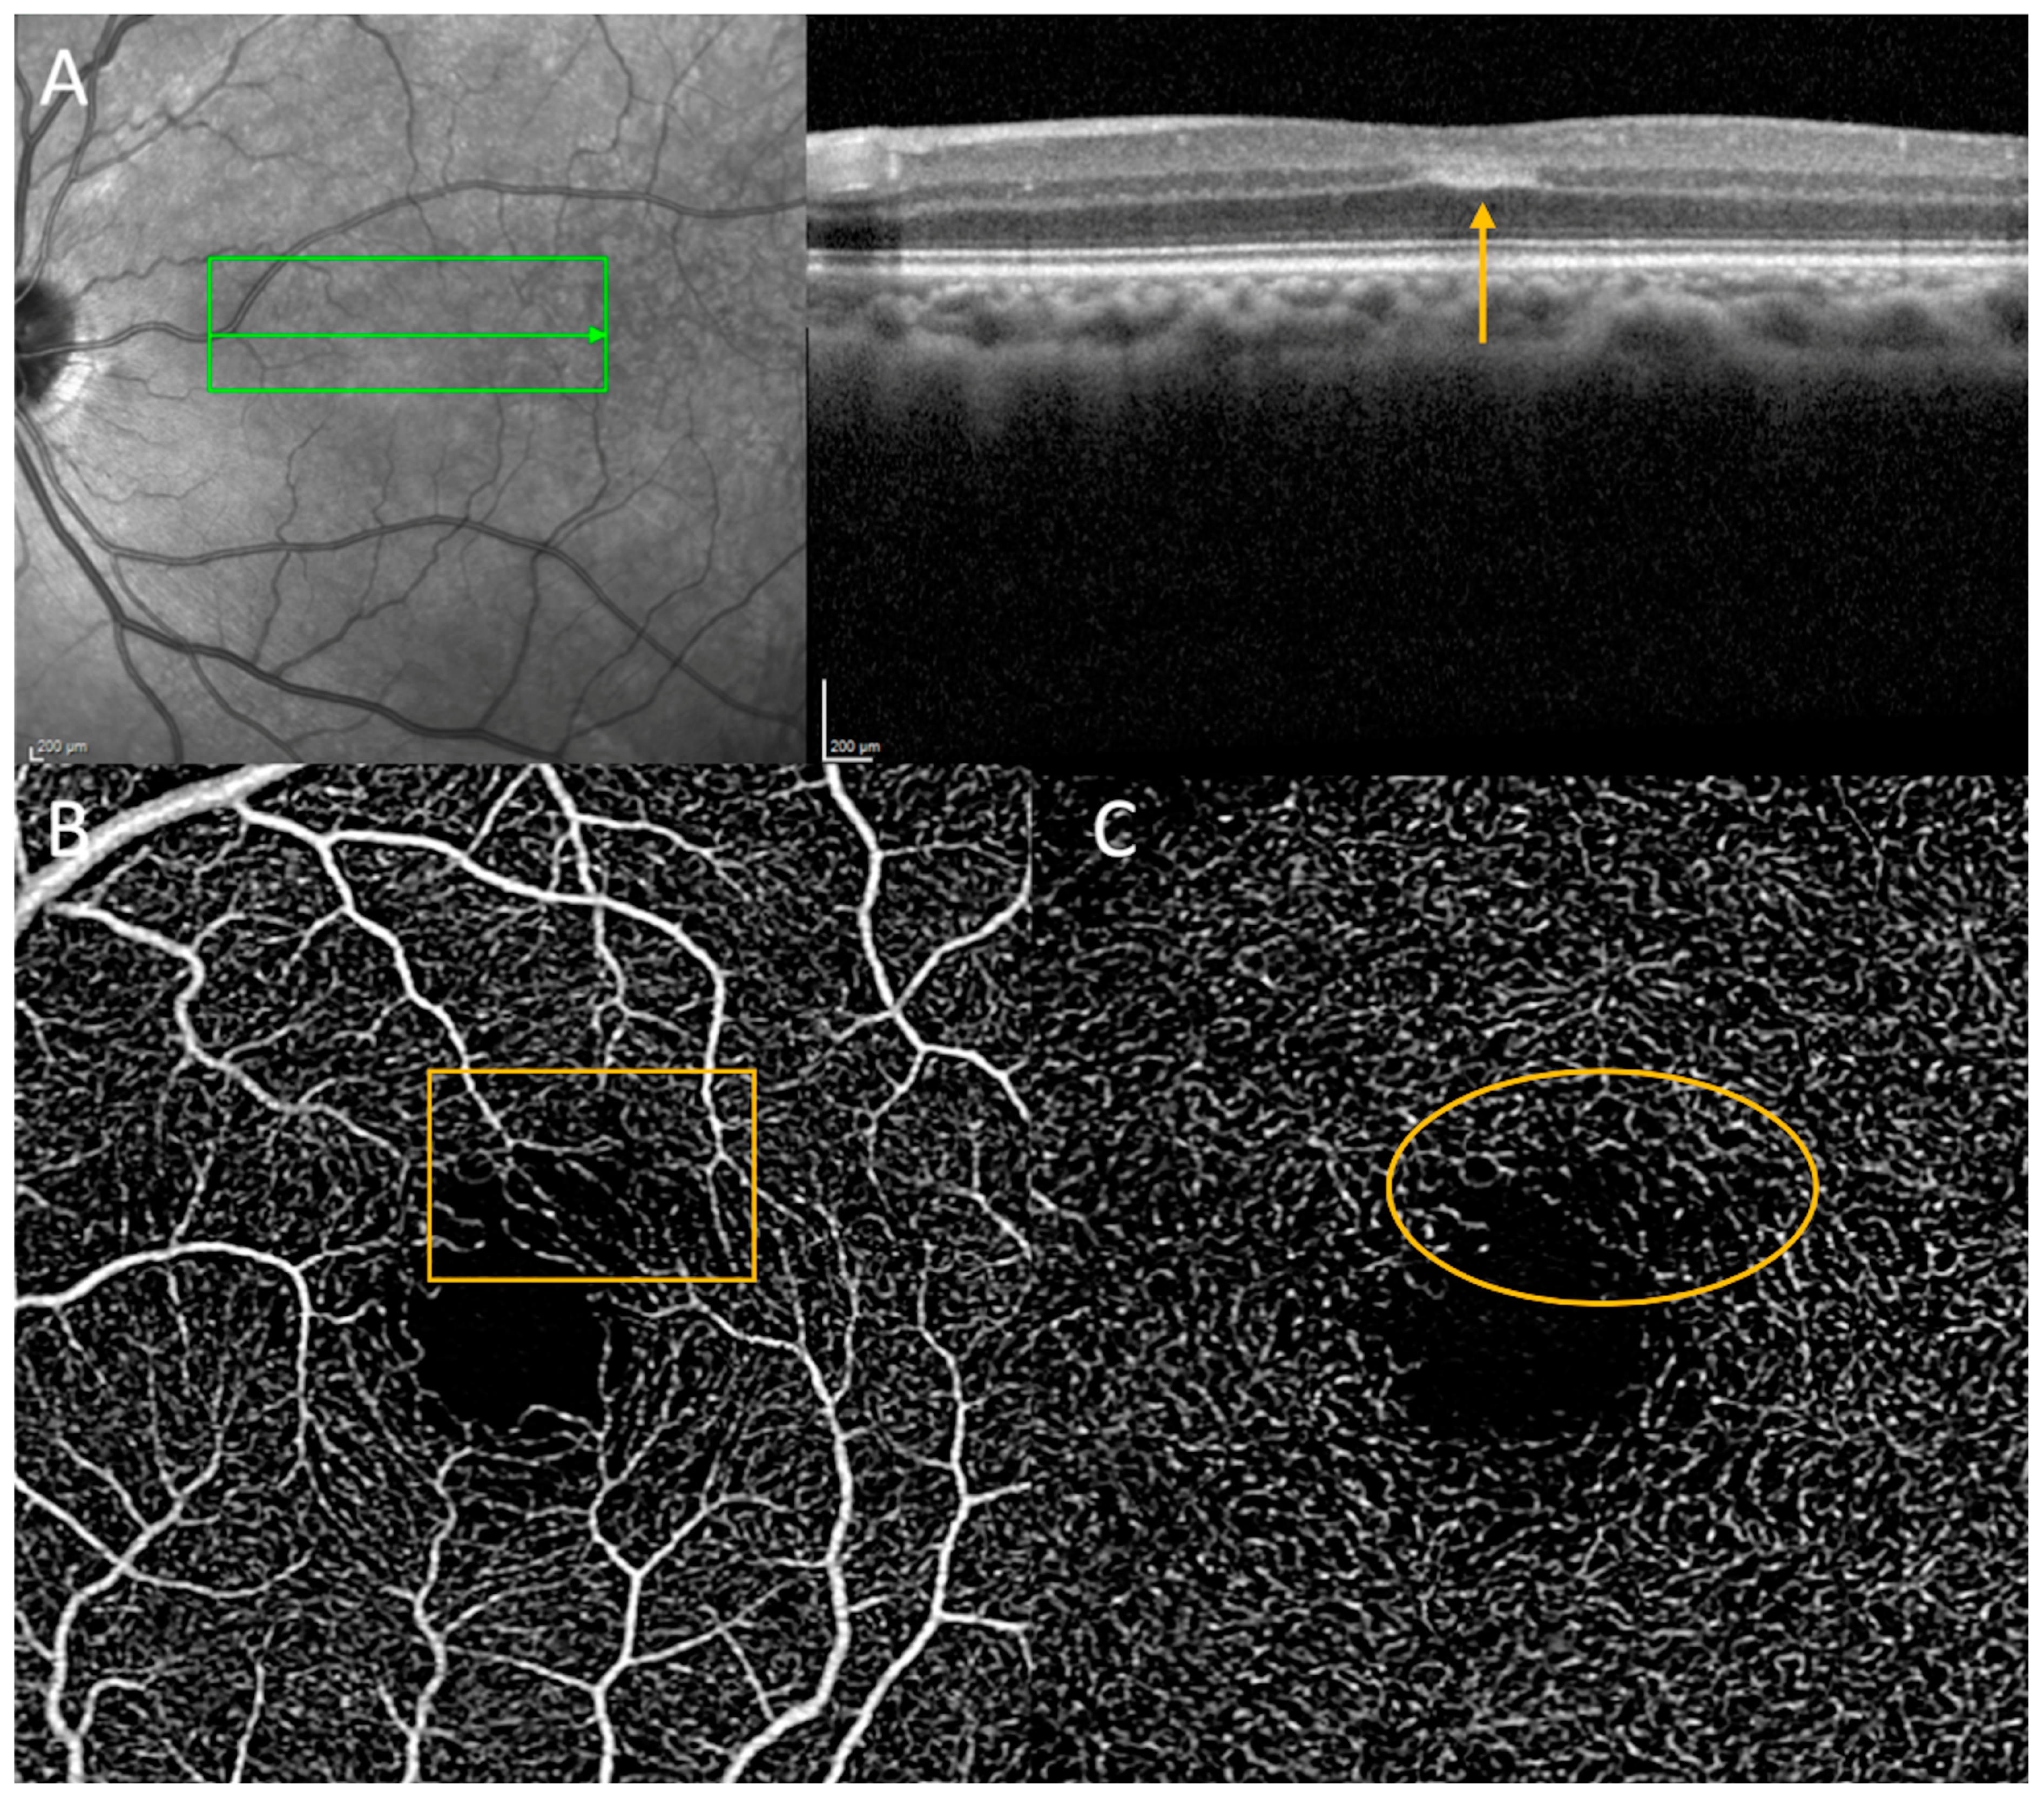

3.3.1. Paracentral Acute Middle Maculopathy

- Chu, S.; Nesper, P.L.; Soetikno, B.T.; Bakri, S.J.; Fawzi, A.A. Projection-Resolved OCT Angiography of Microvascular Changes in Paracentral Acute Middle Maculopathy and Acute Macular Neuroretinopathy. Investig. Opthalmol. Vis. Sci. 2018, 59, 2913–2922. [Google Scholar] [CrossRef] [PubMed]

- Scharf, J.; Freund, K.; Sadda, S.; Sarraf, D. Paracentral acute middle maculopathy and the organization of the retinal capillary plexuses. Prog. Retin. Eye Res. 2021, 81, 100884. [Google Scholar] [CrossRef] [PubMed]

- Long, C.P.; Chan, A.X.; Bakhoum, C.Y.; Toomey, C.B.; Madala, S.; Garg, A.K.; Freeman, W.R.; Goldbaum, M.H.; DeMaria, A.N.; Bakhoum, M.F. Prevalence of subclinical retinal ischemia in patients with cardiovascular disease—A hypothesis driven study. eClinicalMedicine 2021, 33, 100775. [Google Scholar] [CrossRef]

- Madala, S.; Adabifirouzjaei, F.; Lando, L.; Yarmohammadi, A.; Long, C.P.; Bakhoum, C.Y.; Goldbaum, M.H.; Sarraf, D.; DeMaria, A.N.; Bakhoum, M.F. Retinal Ischemic Perivascular Lesions, a Biomarker of Cardiovascular Disease. Ophthalmol. Retina 2022, 6, 865–867. [Google Scholar] [CrossRef]